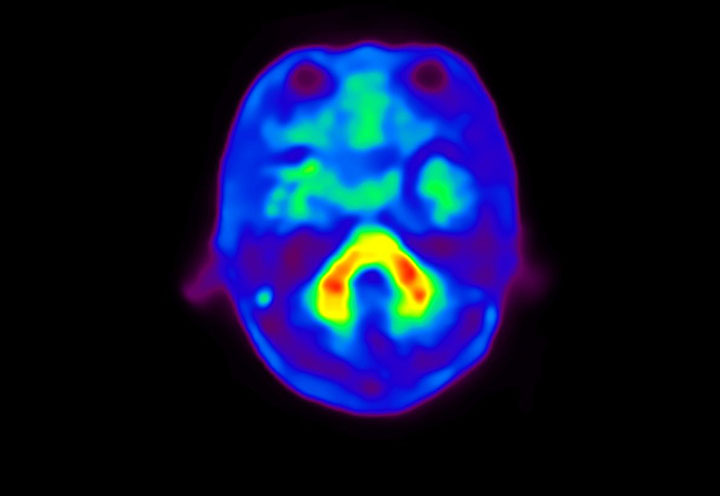

Head / Case4 : Amyloid

Coronal

Courtesy : Kindai University Hospital

- Imaging protocol

- Injected dose: 3.21 MBq/kg, 18F-Flutemetamol

- Uptake time: 100 minutes

- Scan time: 20 minutes